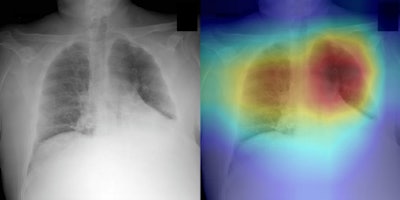

Zhang's group developed an AI algorithm to address the problem of poor diagnostic performance on diagnosing COVID-19 on x-ray. The team trained, validated, and tested a deep neural network called CV19-Net with chest x-rays taken from patients with and without COVID-19. Those patients with the disease had been confirmed for it between February and May of this year, while the group of chest x-rays from patients without COVID-19-induced pneumonia were taken between October and December 2019.

The algorithm performed comparably or better in sensitivity to the radiologist readers; in particular, when the researchers used interpretation results of one particular image from the three readers, they found an averaged AUC of 0.85 compared with the algorithm's AUC of 0.94 on the study test set.